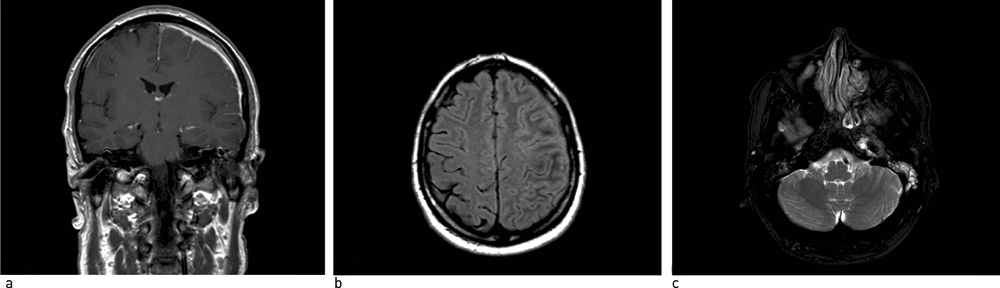

Nye episoder med global hodepine av pressende karakter, CRP-stigning og sensoriske symptomer i høyre kroppshalvdel samt epileptiske anfall i de kommende tre ukene førte til to reinnleggelser med nye antibiotikakurer og oppstart av antiepileptisk medikasjon. Gjentatte cerebrospinalvæskeanalyser viste uendrede funn, infeksiøst agens i cerebrospinalvæsken eller andre kroppsvæsker kunne ikke påvises. MR-kontroll viste økende venstresidig kortikalt hjerneødem. Med tanke på mulig epi- eller subduralt empyem ble det utført eksplorativ kraniotomi med meningeal biopsi. Makroskopisk fant man normalfarget, men hard og tykk dura samt leddblødende subduralt granulasjonsvev. Histologi viste fortykket dura med fibrose og uspesifikt inflammatorisk infiltrat (fig 2). Mikrobiologiske undersøkelser var normale. I et tverrfaglig møte der infeksjonsmedisiner, nevrolog, øre-nese-hals-lege, øyelege, revmatolog, nevrokirurg, nevroradiolog og nevropatolog deltok, ble det konkludert med at pasientens symptomer mest sannsynlig var betinget i intrakranial hypertrofisk pakymeningitt.

For å utelukke sekundær intrakranial hypertrofisk pakymeningitt bør utredningen inkludere meningeal biopsi (2, 18, 20). Ifølge Bang og medarbeidere (8) og Goyal og medarbeidere (14) skal det ved diffus eller skallebasislokalisert intrakranial hypertrofisk pakymeningitt være mulig å stille diagnosen på klinisk grunnlag (positiv MR og effektiv kortikosteroidterapi), mens det ved nodulær intrakranial hypertrofisk pakymeningitt over konveksiteten og ved tvilsomme tilfeller er essensielt med biopsi for å kunne utelukke meningeom og andre neoplasmer. Kupersmith og medarbeidere (3) anbefaler invasiv diagnostikk ved klinisk eller radiologisk forverring under pågående behandling. Histopatologisk undersøkelse av fortykket dura viser uspesifikk inflammatorisk reaksjon i ulike utviklingsfaser, med fibroblastisk infiltrasjon av nøytrofile celler, lymfocytter og plasmaceller (4, 16). Vaskulitt og granulomatøse forandringer er beskrevet (17, 21).